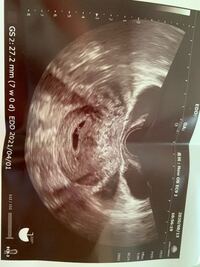

6w1d 心拍確認 ブログ- 6w1dで心拍確認済みの30名のデータ 胎嚢の大きさ:平均193mm 最小115mm 最大241mm (19名) 胎芽の大きさ:平均28mm 最小18mm 最大51mm (21名) 心拍確認済みの30名全員が胎嚢・胎芽の大きさを両方とも公表しているわけではないので、あくまで参考値としてみて 今日で6w1d。 心拍が確認できれば、と思いましたが・・・残念ながら胎芽&心拍は確認できませんでした。 そして改めて胎嚢を子宮内に確認。 前回は「たぶんこれだね~」というレベルでしか確認できてなかったので、今日が私の胎嚢確認日となりました。

妊娠週 6w1d 排卵日が特定できているので、確実に6w1dのエコーです (^^)元気な心拍と2mmの赤ちゃんが確認できました! 2人目の妊娠なので、まだ1歳10ヶ月の長男を抱っこしたり追いかけ回したりでゆっくりできないので、赤ちゃんが心配ですが生命力を信じてAbout Press Copyright Contact us Creators Advertise Developers Terms Privacy Policy & Safety How works Test new features Press Copyright Contact us Creators 6W1Dで心拍確認できず(体外) もうすぐ39歳になるここあです。 初めての顕微授精で人生初の陽性判定をいただきました。 5W3Dで胎のう確認できたのですが、6W1Dで心拍確認できませんでした。 不妊治療クリニックの先生は「6週で見えないのは厳しい